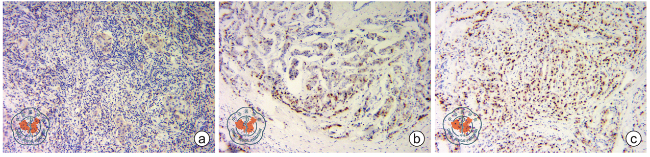

根据最新美国临床肿瘤学会/美国病理医师协会受体检测指南[5],通过免疫组织化学法进行ER和PR检测。核染色<1%为阴性;核染色1%~10%为弱阳性;核染色>10%为阳性。由于ER弱阳性的患者内分泌治疗获益的数据有限,且ER弱阳性癌的生物学行为与ER阴性癌更为相似[5],本研究将ER、PR阳性的界值分别设定为1%、10%和20%(阳性强度的对比见图1图2),在3种划分标准下分别进行分析,规避肿瘤异质性对研究结果的影响。

图1 雌激素受体阳性乳腺癌组织的免疫组织化学染色图(EnVision ×100) a~c图分别所示雌激素受体1%阳性、 10%阳性、 20%阳性

图2 孕激素受体阳性乳腺癌组织的免疫组织化学染色图(EnVision ×100) a~c图分别所示孕激素受体1%阳性、 10%阳性、 20%阳性